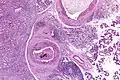

| Low magnification micrograph of a salivary duct carcinoma with characteristic comedonecrosis (left of image) adjacent to normal parotid gland (right of image). H&E stain. | |

Their histologic appearance is similar to ductal breast carcinoma.

Very low mag.